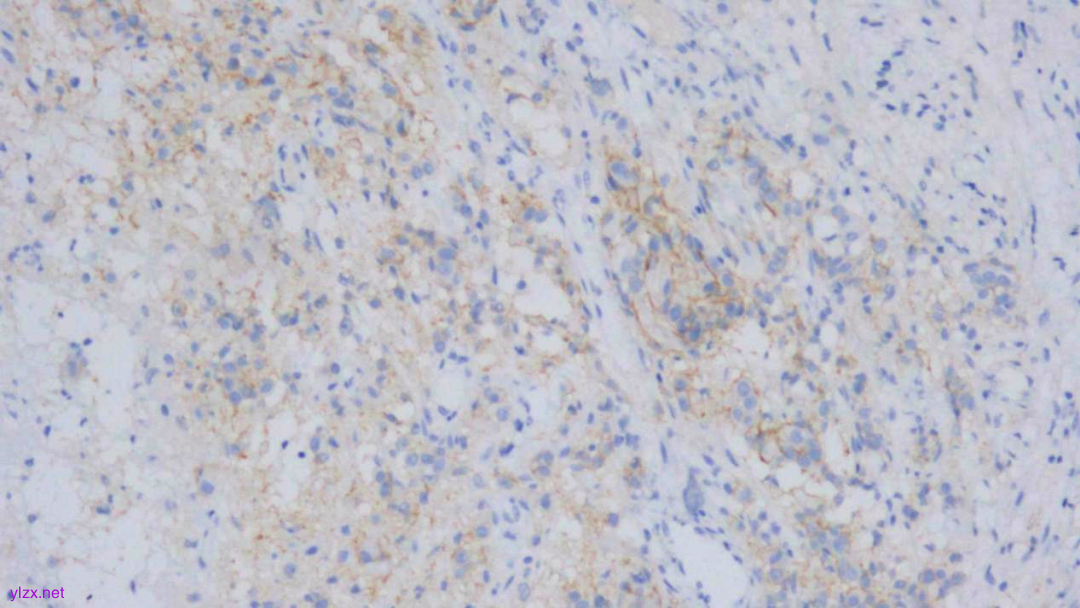

HE:

黏膜间质内见胞浆丰富,红染及粉染瘤细胞弥漫分布,部分细胞核稍偏位,核圆形,稍增大,深染,见核仁,穿插在固有腺之间,伴少量炎细胞浸润。

瘤组织穿插在固有腺之间,较弥漫,核稍增大,深染

瘤细胞稀疏排列,胞浆粉染及红染,宽阔

瘤细胞核圆形,见核仁,部分细胞核偏位,未见核分裂象

瘤细胞核仁明显

IHC结果:

CK(AE1/AE3)(+)、GATA3(+)、P120(浆+)、E-Cadherin(-)、CK7(+)、CK-H(+)、CAM5.2(+)、CK20(-)、CEA(poly)(-),P53(约40% 弱+),Ki-67(约1%+)

病理诊断:

(胃窦)腺癌,HE形态结合临床病史、免疫组化结果,符合乳腺浸润性小叶癌转移。